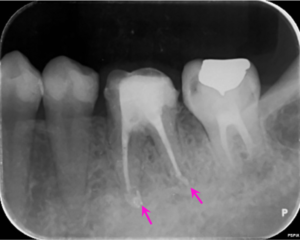

根の治療1か月後にグラスファイバーの芯棒を用いた歯の土台(根の治療を行った場合に行う治療です)を立てた際のレントゲン写真です。まだ根の先の骨の溶けている部分の大きさは変わりません。

根の治療2か月後のレントゲン写真です。矢印の部分の骨の溶けている部分の大きさが小さくなっています。

根の治療4か月後のレントゲン写真です。骨の溶けている部分の透過性(黒さ)が改善して(薄くなって)、治癒に向かっている様子がうかがえます。治療後から咬む際の痛みなどの症状は無くなり、治療後2カ月で仮歯を装着されています。

根の治療9か月後のレントゲン写真です。矢印の根の先の骨の溶けている部分は無くなっています。この後、仮歯からジルコニア製のかぶせを装着されました。